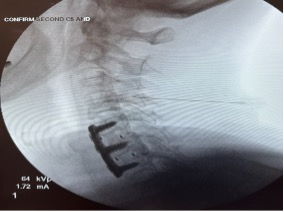

• X-rays, CT scan, MRI or EMG and helps to make the diagnosis.